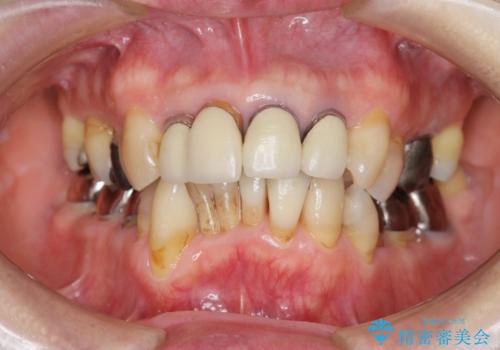

矯正治療とセラミック治療で口腔内環境を劇的に改善